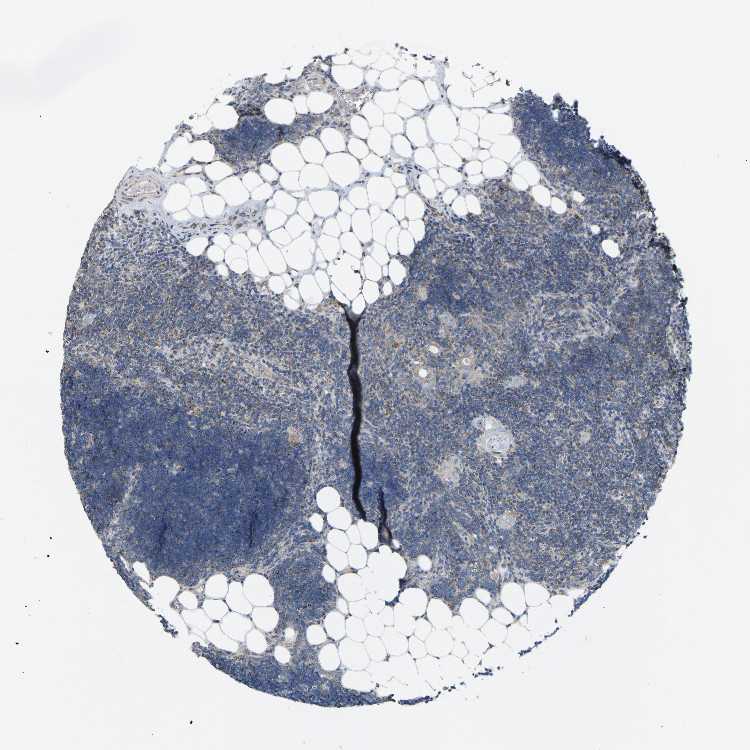

TISSUE PRIMARY DATA LYMPH NODE Show tissue menu

Lymph node

LYMPH NODE - Antibody stainingi

Antibody staining in the annotated cell types in the current human tissue is reported as not detected, low, medium, or high, based on conventional immunohistochemistry profiling in selected tissues. This score is based on the combination of the staining intensity and fraction of stained cells.

Each image is clickable and will lead to virtual microscopy that enables deeper exploration of all samples and also displays staining intensity scores, fraction scores and subcellular localization as well as patient and tissue information for each sample.

Antibody HPA017925Antibody CAB001944

Germinal center cells Low-

Non-germinal center cells MediumMedium